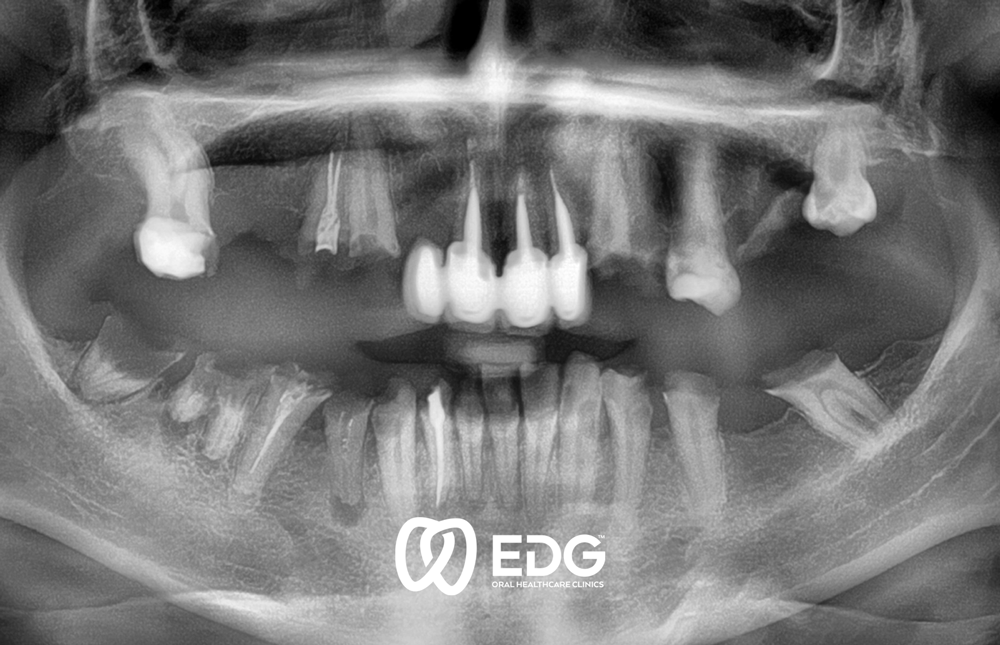

Губењето на забот може да се должи на различни причини: кариес, пародонтопатија или од повреда. Во одделот за протетика, на нашите пациенти им нудиме современа нега, со што се воведуваат естетски и функционални стандарди и индивидуални барања. Инсистираме на неразделна врска помеѓу формата и функцијата на стоматолошката протетика. Само функционално добрата работа доведува до добри естетски резултати. За избор и изработка на забна протеза, објективните критериуми играат улога, како и типот и возраста на пациентот. Комплексната протетска реконструкција на забите бара прецизна и обемна дијагностика пред да се започне со реконструктивни мерки. За да го направите ова, неопходна е темелна медицинска анамнеза, како и РТГ дијагностика и употреба на современи методи за точно утврдување на положбата на забите и движењето на зглобот на темпоромандибуларниот (виличниот) зглоб. За протетска реставрација, користиме модерна технологија за коронки и мостови, делумни и целосни протези и импланти.